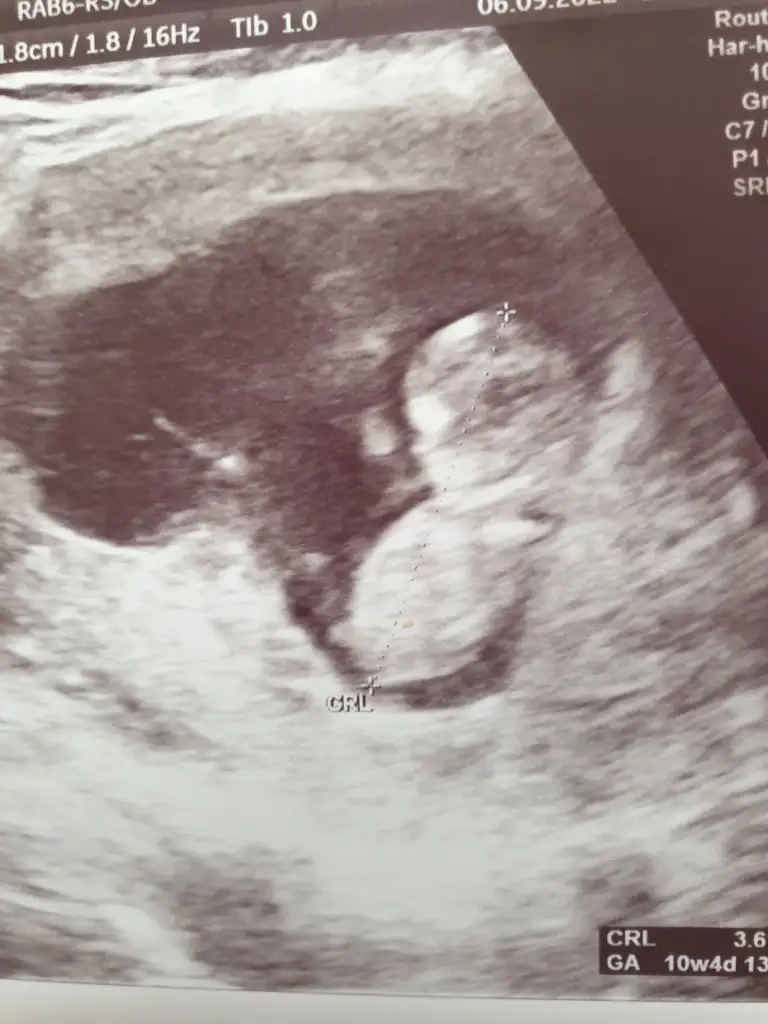

Merhaba bana da tahminde bulunurmusunuz lütfen 🥰🙏 10+4 ve 10+6 karindan ultrason fotolari. 1. Resimdekini pipi zannetmistim meğer ayağiymiş 😅🙈

20220906_175540.webp 20220905_160108.webp